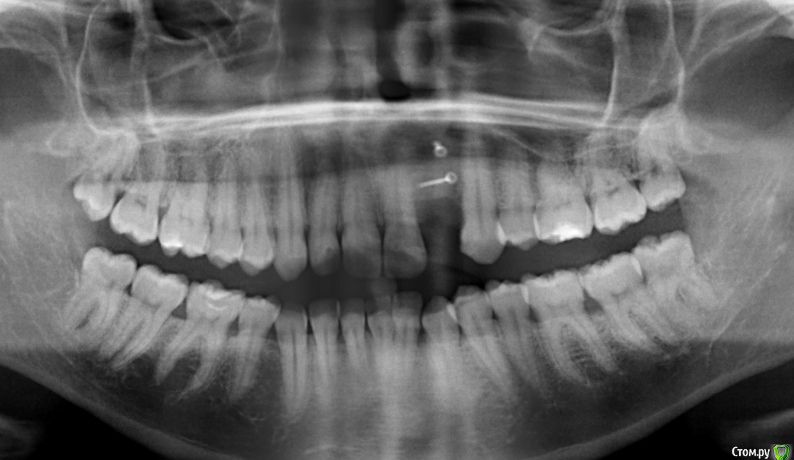

LuBoF Опубликовано 23 марта, 2015 Поделиться Опубликовано 23 марта, 2015 (изменено) Добрый день. 4 месяца назад была проведена операция по пересадки костного блока с нижней челюсти. На осмотре стоматолог сказал, что кости не достаточно и необходимо повторить процедуру.Так ли необходима эта оперция, нельзя расчитывать уже на имплант? Нельзя ли было сразу наростить необходимый объем костной ткани за одну операцию, а то это "удовольствие" болезненное и не из дешевых? И какой лучше выбрать способ подсадки: опять своей костью или можно искусственной?Ниже прикрепляю снимок.Спасибо. Изменено 23 марта, 2015 пользователем LuBoF Ссылка на комментарий

Bier Опубликовано 24 марта, 2015 Поделиться Опубликовано 24 марта, 2015 этот снимок не дает необходимого нам третьего измерения - толщины альвеолярного гребня.Только высоту и ширину. Надо трехмерный - КТ Ссылка на комментарий

Bier Опубликовано 25 марта, 2015 Поделиться Опубликовано 25 марта, 2015 да ) но 2х измерений мало ) Ссылка на комментарий